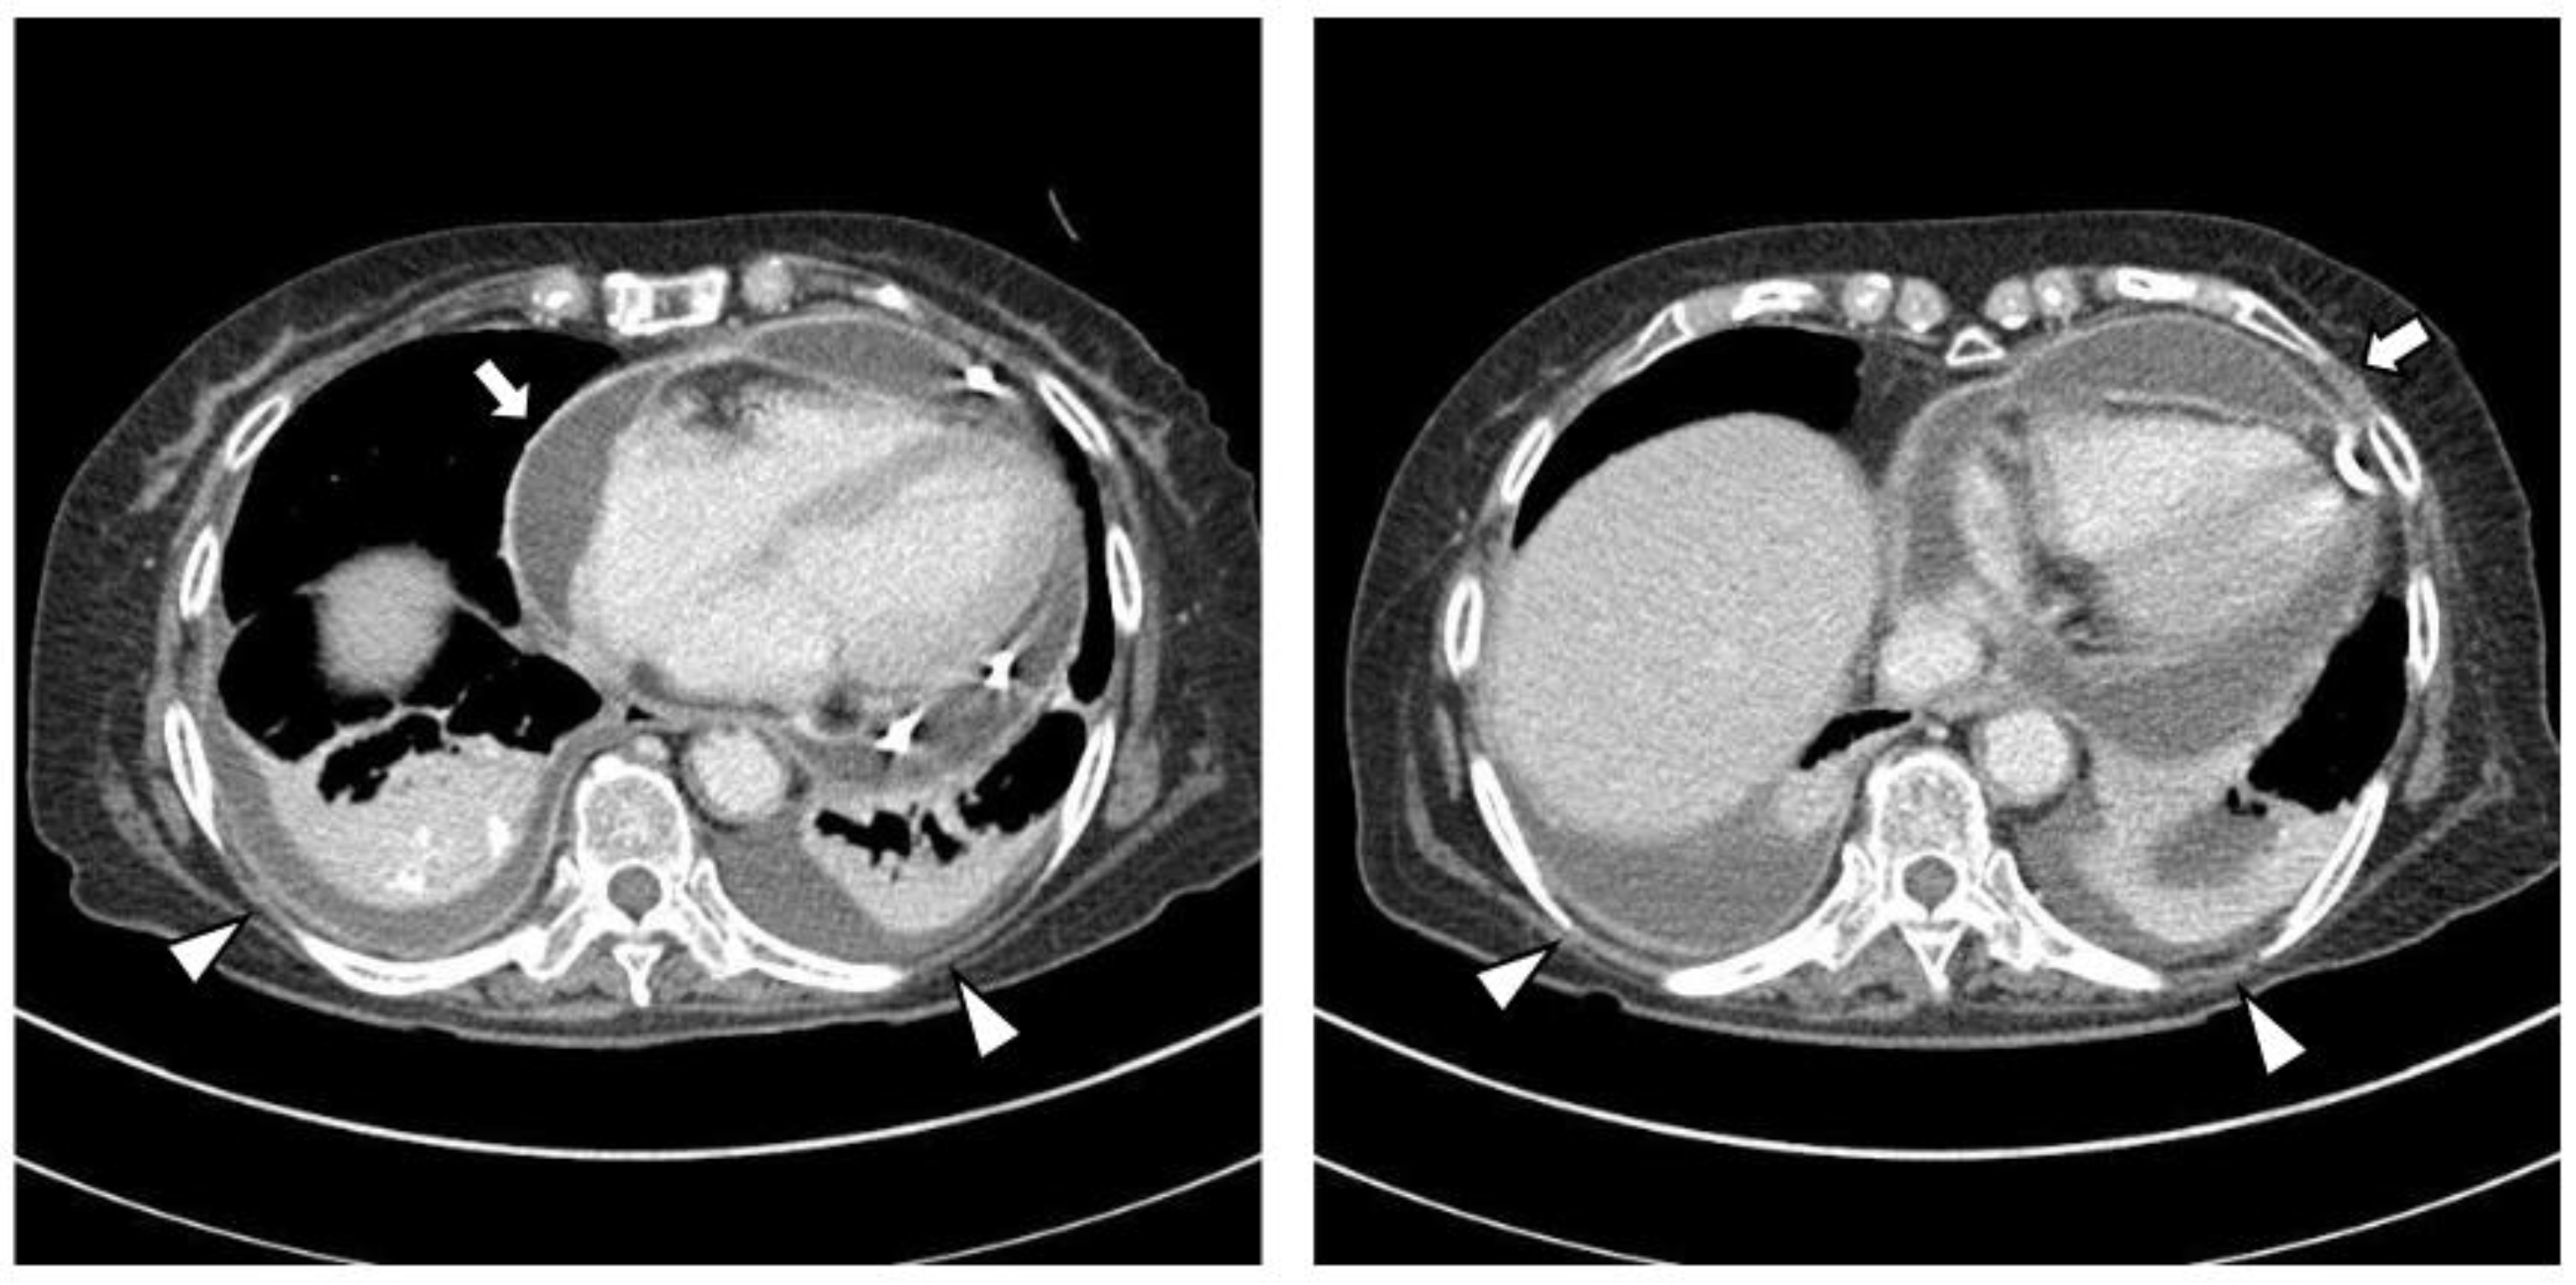

Figure 3.

Upon abdominal computed tomography, there is fluid collection in both perirenal spaces (white arrowheads) and cortical scarring in the upper pole of the right kidney (black arrows), which is sequelae of recurrent urinary tract infection of the right kidney. There are findings of diffuse renal involvement, which are non-specific findings of medical renal disease, but there is no evidence of distant metastasis.